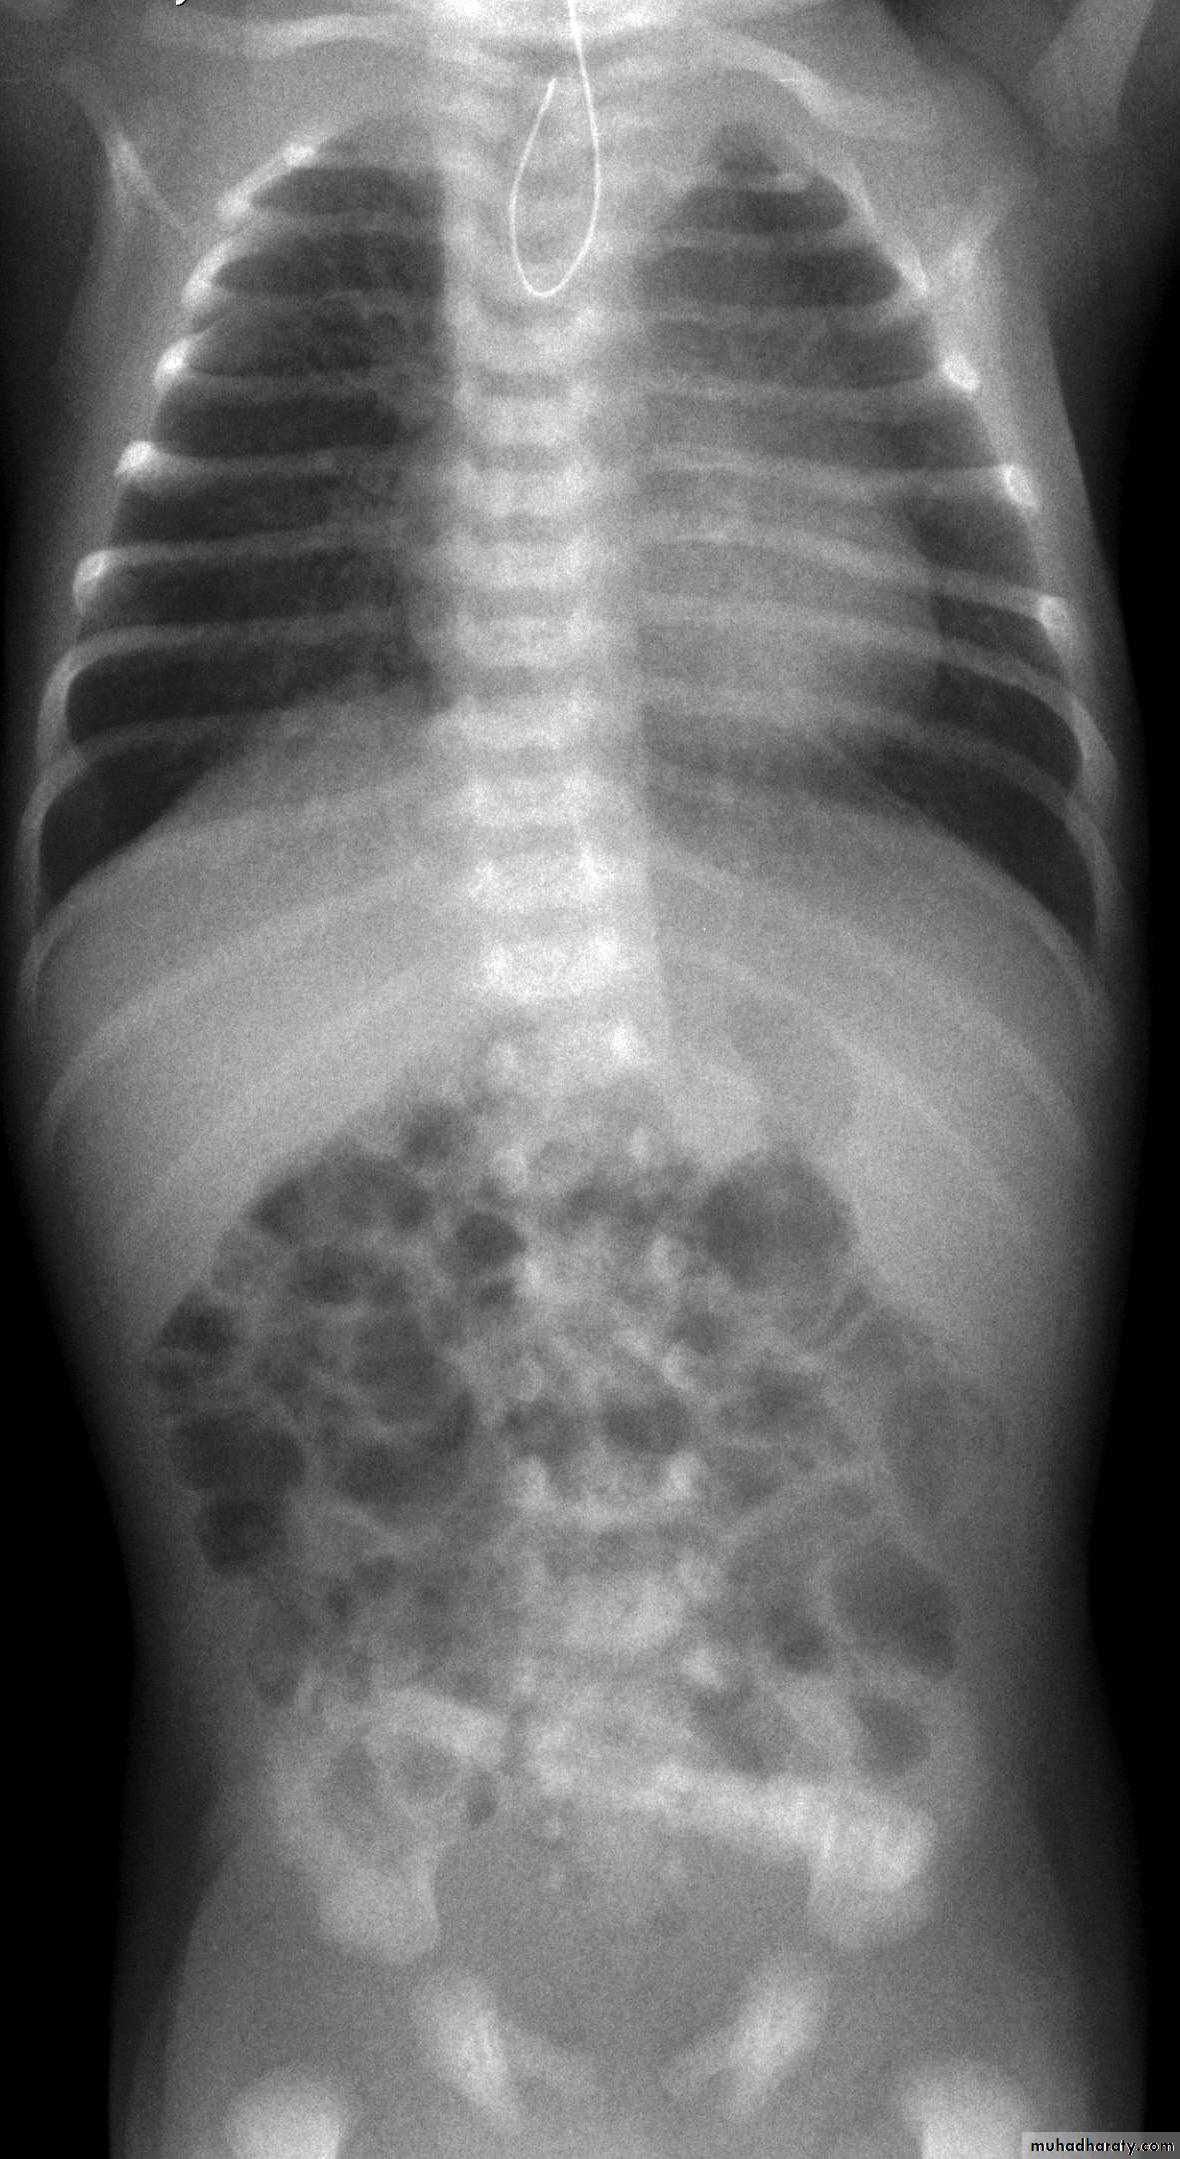

CausesEsophageal atresia

Types:• isolated atresia 8%

• Proximal fistula with distal atresia 1%

• Proximal atresia with distal fistula 85%

• Double fistula with intervening atresia 1%

• Isolated fistula [H-type] 4%